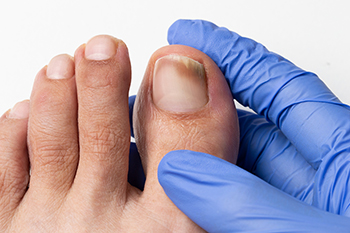

Toenail fungus can cause the toenails to become brittle and yellow. They can gradually harden and become thicker, causing difficulty in having them properly trimmed. This unsightly foot condition is caused by a fungal infection, and is considered to be contagious. This type of fungus lives and thrives in warm and moist environments, consisting of shower room floors, public swimming pools, and similar areas. The fungus can enter the body through tiny cracks in the skin, and it is beneficial to wear appropriate shoes while in these types of areas. A diagnosis is performed by extracting a small sample of the nail. After confirmation is received, treatment can begin. There are various methods that can accomplish this, and it is strongly suggested a podiatrist is contacted as quickly as possible who can prescribe proper medication.

For more information about treatment, contact Akena Wannamaker, DPM of ASW Foot and Ankle. Our doctor can provide the care you need to keep you pain-free and on your feet.

Toenail Fungus Treatment

Toenail fungus is a condition that affects many people and can be especially hard to get rid of. Fortunately, there are several methods to go about treating and avoiding it.

Antifungals & Deterrence

Oral antifungal medicine has been shown to be effective in many cases. It is important to consult with a podiatrist to determine the proper regiment for you, or potentially explore other options.

Applying foot powder on the feet and shoes helps keep the feet free of moisture and sweat.

Sandals or open toed shoes – Wearing these will allow air movement and help keep feet dry. They also expose your feet to light, which fungus cannot tolerate. Socks with moisture wicking material also help as well.

If you have any questions please contact our office located in Richmond, VA . We offer the newest diagnostic and treatment technologies for all your foot and ankle needs.